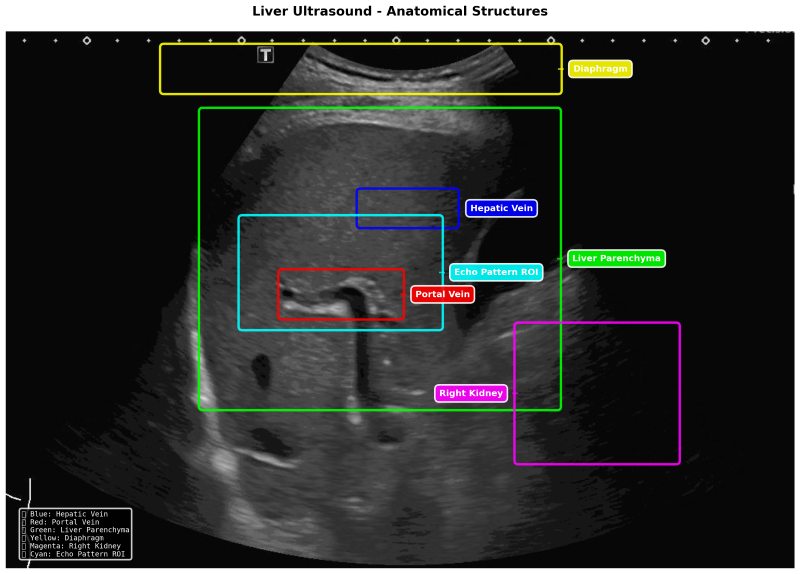

SmartLiva ทำงานเหมือน “อัปเกรด” จากภาพอัลตราซาวด์ขาวดำธรรมดาให้กลายเป็นผลวินิจฉัยที่อ่านง่ายและแม่นยำ โดยอัปโหลดภาพผ่านเว็บได้ทั้งบนคอมพิวเตอร์หรือแท็บเล็ต จากนั้นระบบจะช่วยปรับภาพให้ชัดขึ้น คัดเฉพาะบริเวณเนื้อตับที่ต้องวิเคราะห์ และทำให้ภาพดูเข้าใจง่ายขึ้นด้วยการไฮไลต์เป็นสี (เช่น ตับเป็นสีแดง ไขมันเป็นสีเหลือง) เพื่อให้เห็นความผิดปกติได้ทันที โดย AI จะทำการประเมิน 3 เรื่องพร้อมกัน คือ ประเมินระดับพังผืด/ความแข็งของตับ (F0–F4), ตรวจหาความผิดปกติของเนื้อเยื่ออย่างถุงน้ำหรือมะเร็งตับ และตรวจหาพยาธิใบไม้ตับ ซึ่งตัว AI จะทำการประมวล วิเคราะห์ และสรุปผลออกมาเป็นรายงานพร้อมภาพประกอบและคำอธิบายที่คนทั่วไปเข้าใจได้